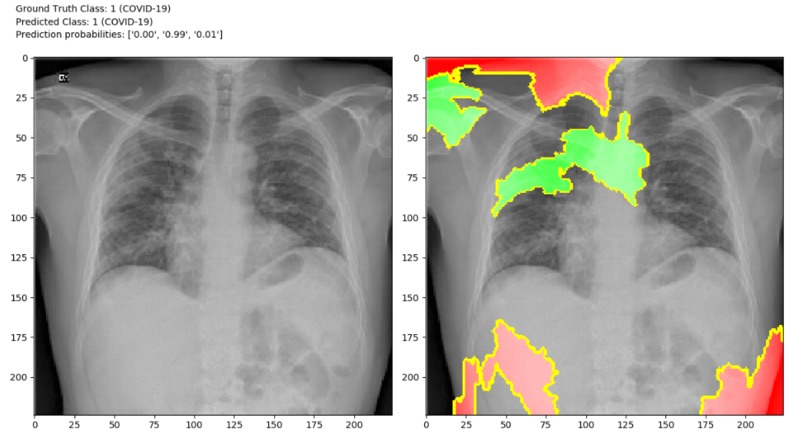

Although there is one drawback that X-ray analysis requires a radiology expert and takes significant time. Which is precious when people are sick around the world. Therefore, developing an automated analysis system is requires to save medical professionals valuable time.we can identify the difference in those two images. So, we can create a software which can identify difference between those two images using image processing techniques and Artificial Intelligence. We can Train AI model with features of normal person’s X-ray data and COVID19 patient’s X-Ray image data.

Detection of COVID19 symptoms is not only essential but also difficult task as it is current pandemic. COVID19 affects the lungs so if we detect in few seconds it will save doctors and health workers valuable time.

The primary objective is to develop the automated system that will detect the symptoms of COVID19 using X-Ray image.The secondary objective is to identify case of COVID19 positive or negative. Our goal is to use X-ray or CT images to develop AI based approaches to predict and understand the infection. We will release these models using our open source Chester AI Radiology Assistant platform which is designed to scale to a global need by performing the computation locally.